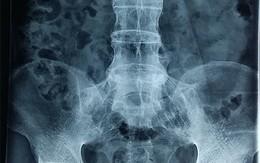

Đau thần kinh tọa

Thần kinh tọa hay còn gọi là dây hông to là một dây thần kinh chạy từ phía dưới của lưng vùng hố chậu đến phía sau mỗi chân.

5 nguyên nhân gây đau thần kinh tọa

Đau thần kinh tọa biểu hiện đau tại cột sống thắt lưng lan tới mặt ngoài đùi, mặt trước ngoài cẳng chân, mắt cá ngoài và tận ở các ngón chân.